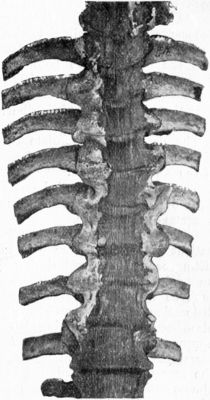

| 210. | Tuberculous Osteomyelitis affecting several Vertebræ at Thoracico-Lumbar Junction | 432 |

| 211. | Osseous Ankylosis of Bodies (a) of Dorsal Vertebræ, (b) of Lumbar Vertebræ following Pott's Disease | 434 |

| 212. | Radiogram of Museum Specimen of Pott's Disease in a Child | 435 |